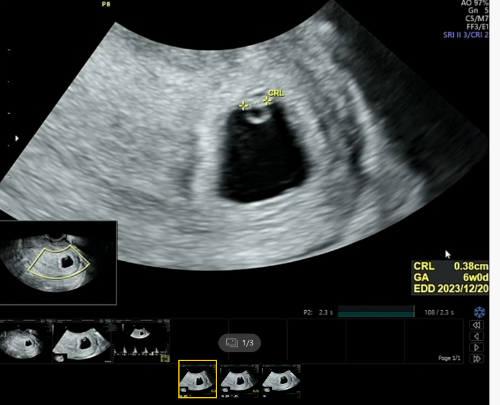

그리고 다녔던 난임병원에 다시 들러 6주 0일 아기집, 난황, 심장소리를 확인했습니다.

6주 3일 일 줄 알았는데, 알고보니 6주사이즈 정도였고 이는 안정기가 될 때 까지 몇일정도 차이날 수 있다고 합니다.

난황에 가려져 잘 보이지 않는 아기, 아기는 지금 매우매우 작은 0.38cm의 모습을 하고 있답니다.

너무 신기하죠? 출산 예정일은 2023년 12월 20일로 보여지네요.

6주 심장소리는 103부터 126bpm까지가 정상범위이고요.

제가 6주 0일차에 100bpm 정도였으니, 살짝 낮은 정도이긴 하지만